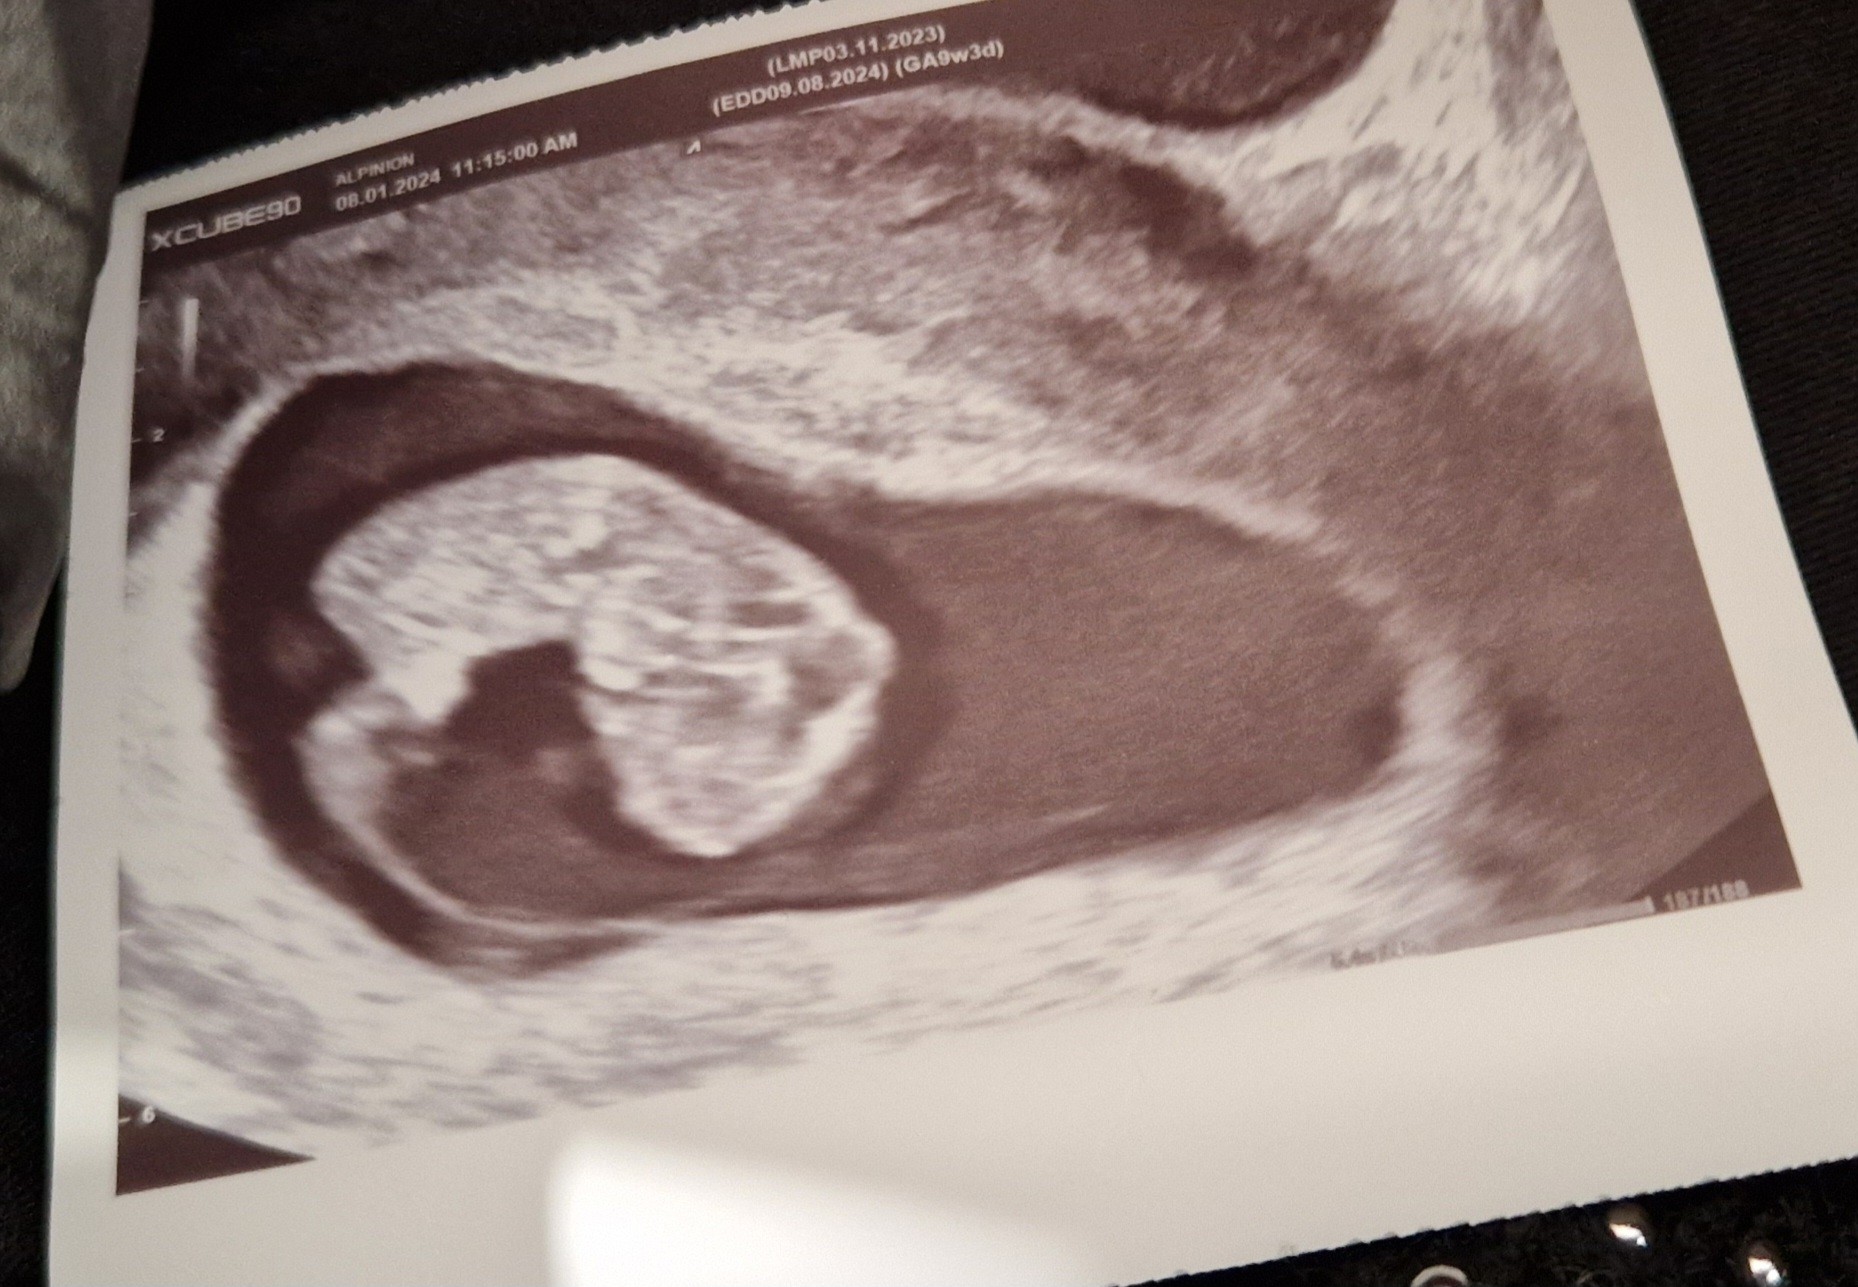

Dziewczęta wy tak rozmawiacie o badaniach, a ja w sumie też za tydzień mam 1 prenatalne. Może dowiem się już kto mieszka w brzuchuw 1 ciąży już było widać że chłopczyk